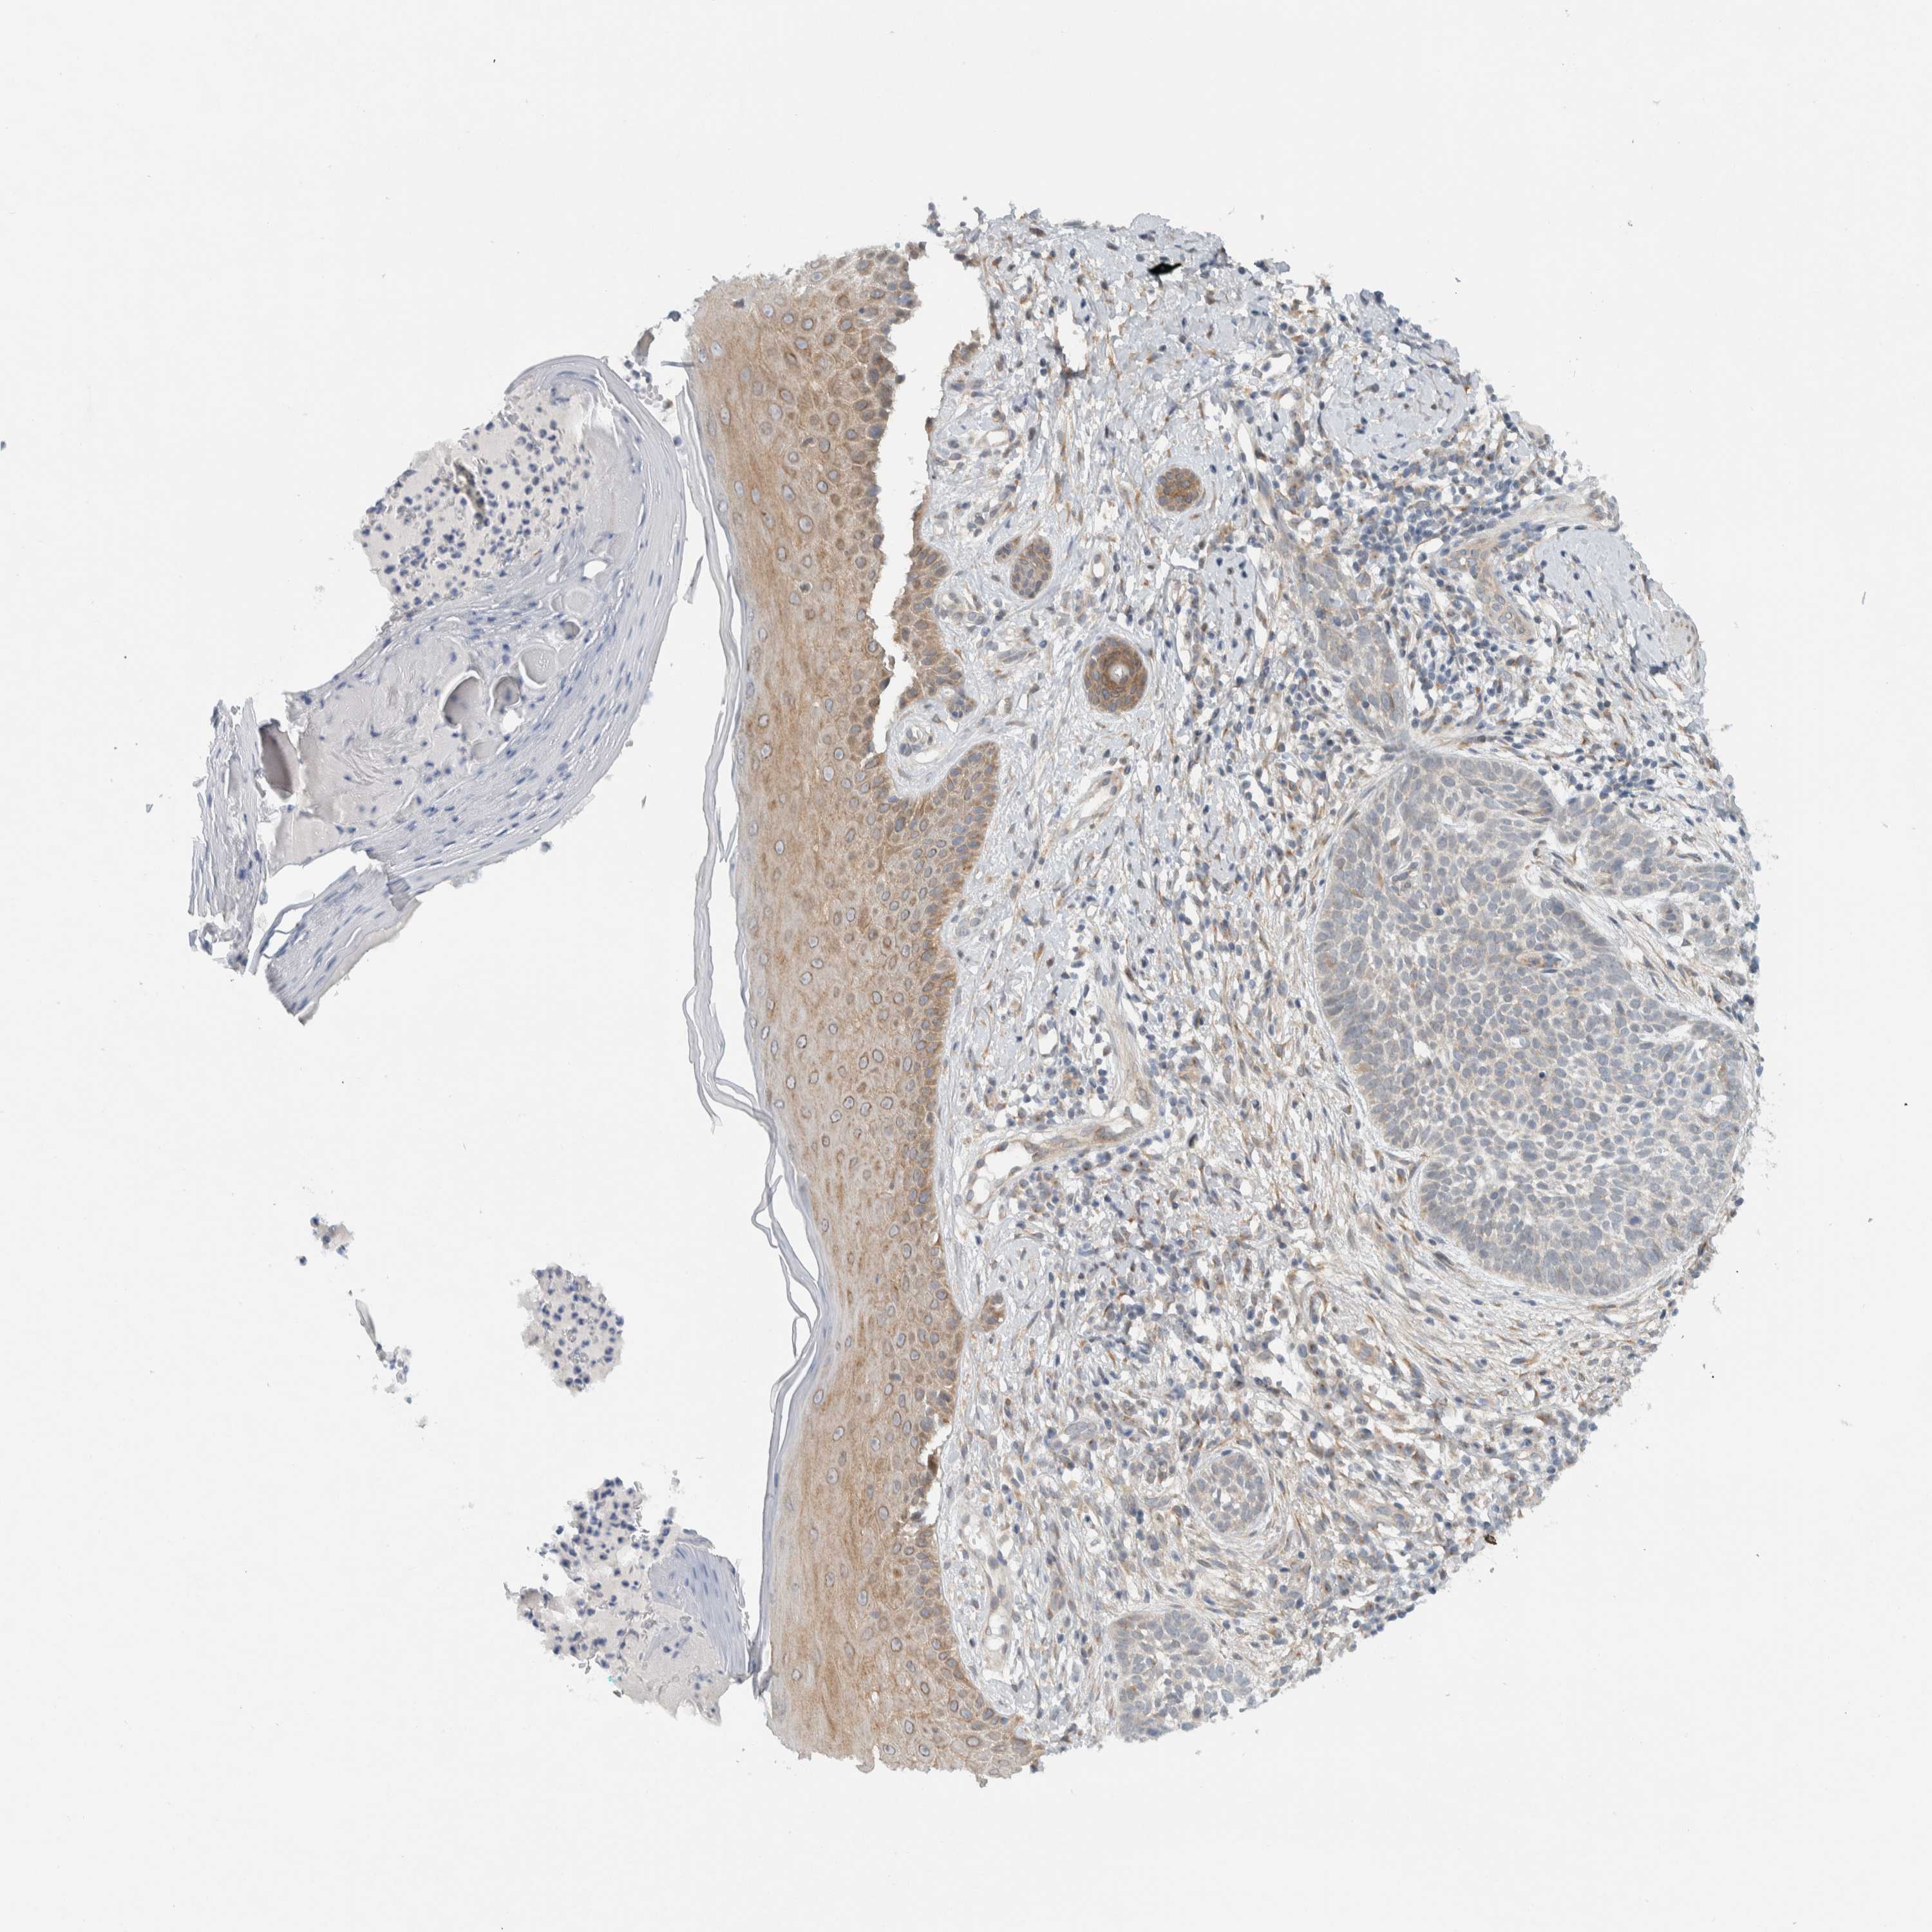

Basal cell and squamous cell cancer

SKIN CANCER - Protein expressioni

A mouse-over function shows sample information and annotation data. Click on an image to view it in a full screen mode. Samples can be filtered based on level of antibody staining by selecting one or several of the following categories: high, medium, low and not detected. The assay and annotation is described here.

Antibody stainingi

Antibody staining in the annotated cell types in the current human tissue is reported as not detected, low, medium, or high, based on conventional immunohistochemistry profiling in selected tissues. This score is based on the combination of the staining intensity and fraction of stained cells.

Each image is clickable and will lead to virtual microscopy that enables deeper exploration of all samples and also displays staining intensity scores, fraction scores and subcellular localization as well as patient and tissue information for each sample.

Antibody HPA024093

Staining

High

Medium

Low

Not detected

Intensity

Strong

Moderate

Weak

Negative

Quantity

>75%

75%-25%

<25%

None

Location

Nuclear

Cytoplasmic/membranous

Cytoplasmic/membranous,nuclear

Squamous cell carcinoma, NOS